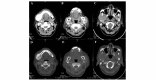

Mandibular metastatic carcinoma is a rare lesion that accounts for <1% of all oral malignancies. To provide greater experience in this field, the present study was conducted in which 6 cases of mandibular metastatic carcinoma were retrospectively reviewed. The origin of the lesions was the prostate in 2 cases, the lungs in 2 cases, the breast in 1 case and the thyroid gland in 1 case. The clinical and computed tomography features, surgical management and follow-up outcomes were investigated. The study indicated that surgeons should include the suspicion of metastasis in the differential diagnosis for mandibular tumor, particularly in patients who have a history of malignancy. A poor prognosis was associated with the examined patients. To extend the survival time as long as possible, a treatment strategy using multiple therapies, including segmental mandibulectomy, radiotherapy and chemotherapy, is recommended.